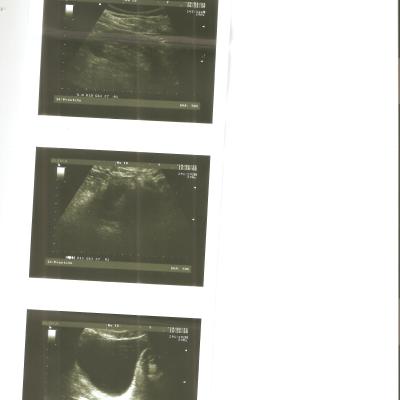

Здравствуйте, вот уже на протяжении полутора лет не могу выяснить причину своего недуга, обошел кучу урологов и венерологов и никто из них не смог мне помочь. Все началось с того, что у меня появилось жжение в уретре после эякуляции, при мочеиспускании боли и жжения не было, только после эякуляции. Походил я по урологам, делал трузи простаты, сдавал на иппп, сдавал секрет простаты и по заверению врачей все у меня нормально. В итоге я не выдержал и самостоятельно проставил себе курс свечей "Виферон" и о чудо, они мне помогли, жжение полностью ушло, но спустя два месяца стал ощущать подергивания в уретре и при пальпации ощущается боль, в основном боль у начала уретры под яичками, но и в середине уретры тоже есть подергивания и покалывания, губки уретры чуть припухшие и красноватые. При мочеиспускании боли нет, эрекция хорошая. Прикрепляю все свежие анализы и исследования к данному сообщению.